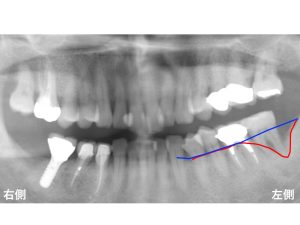

骨吸収の状態を線で記載してみましょう!

以下の青線は、

もともと骨があった位置です。

骨吸収する前は、この位置まで骨があったのです。

現在は、赤線まで骨吸収が進行してしまっています。

青線と赤線を重ねると以下になります。

骨吸収が生じた部分が以下の赤の領域です。

かなりの骨吸収があることが分かります。